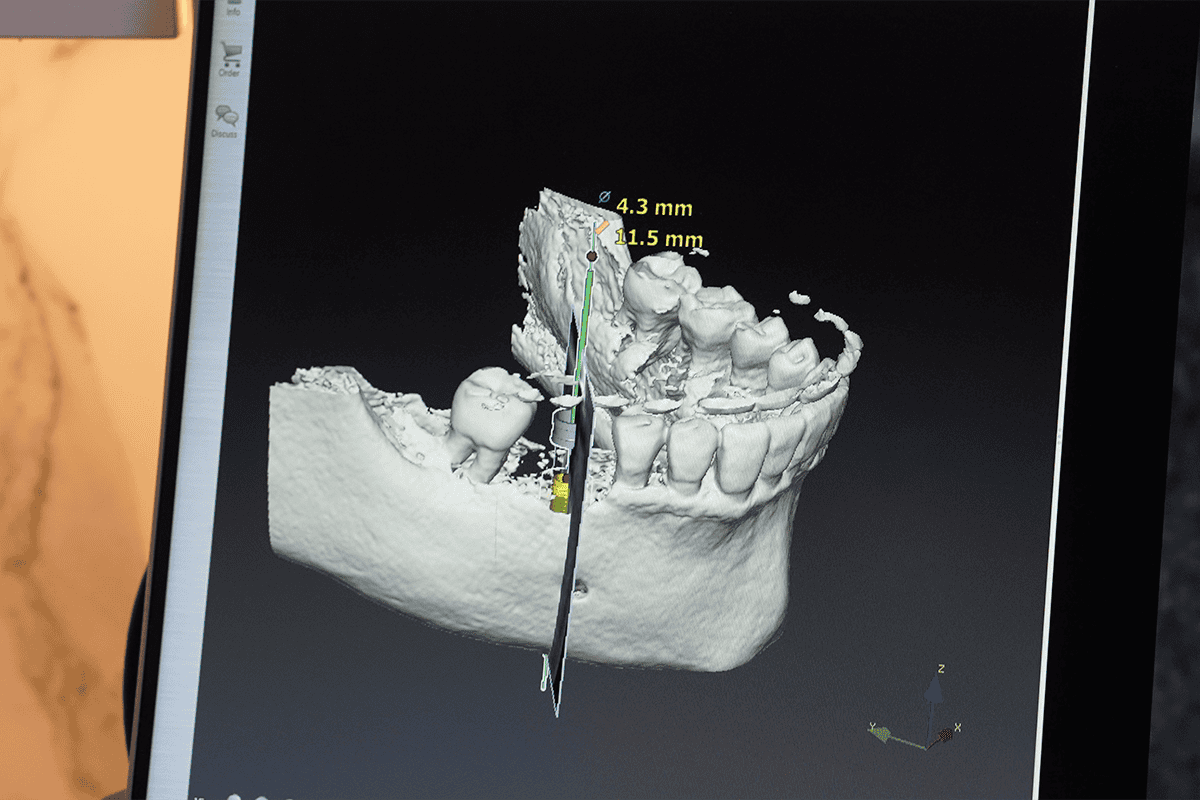

Dental implants are a slightly more invasive surgical procedure compared to many other dental treatments. They involve the precise placement of titanium implant posts into the jawbone to serve as artificial tooth roots, onto which dental prosthetics like crowns, bridges, or dentures are securely anchored. The intricacy of this process highlights the importance of experience in the field, as it can significantly impact the success and comfort of the implantation procedure.

5. Do they have a full surgical setup?

A fully equipped surgical setup is essential for performing dental implant procedures safely and effectively. Ensure that your chosen dentist has access to the necessary equipment and facilities.